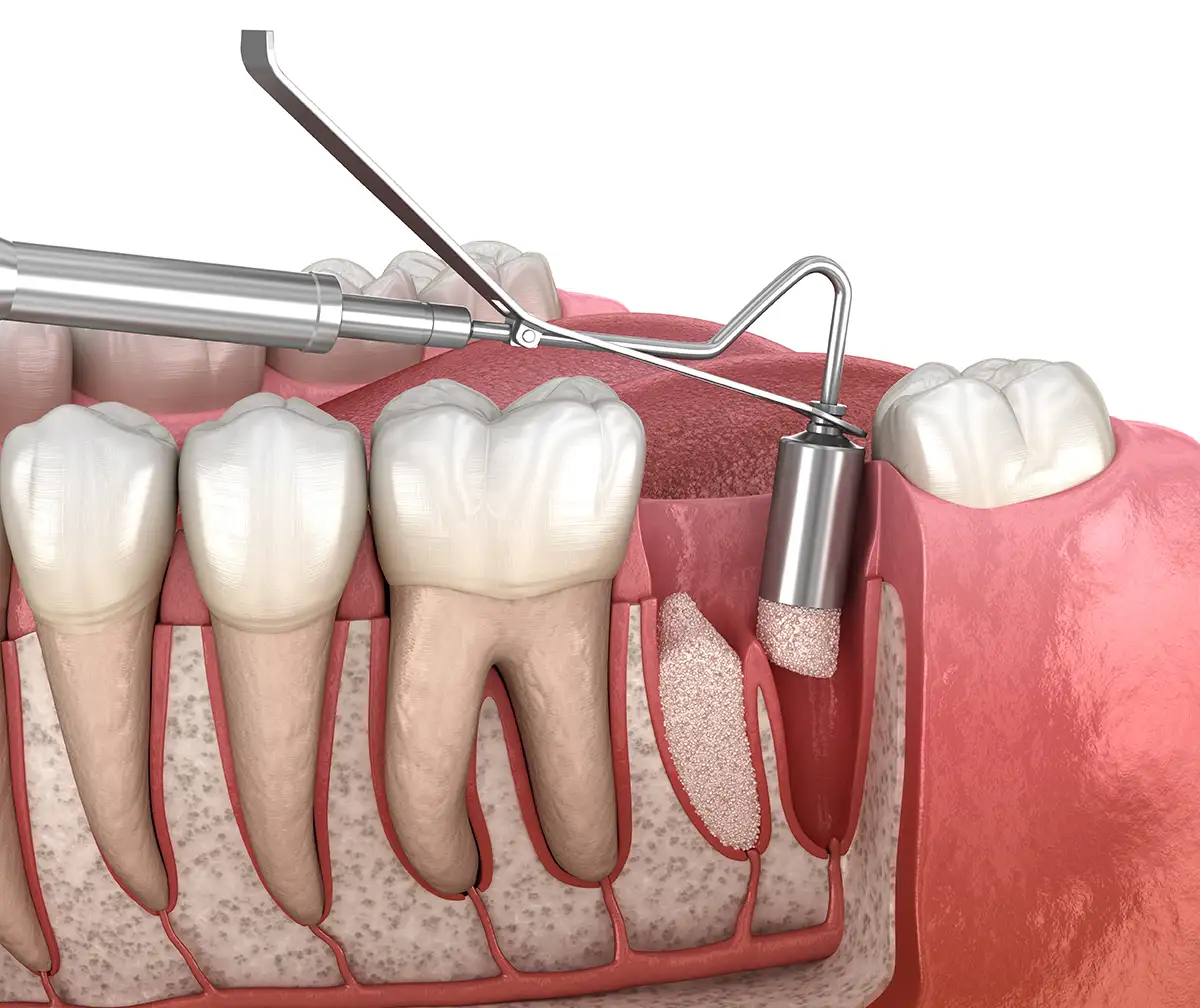

En muchas ocasiones observamos por medio de radiografías tridimensionales como los escáner CBCT o a simple vista en intervenciones quirúrgicas, la ausencia de hueso en los dientes o alrededor de los implantes.

En estos casos es muy importante realizar una regeneración de hueso para conseguir resultados exitosos a largo plazo.

Además, tras realizar la extracción de un diente sabemos que se va a producir una remodelación ósea, perdiéndose gran cantidad de hueso en dicha zona. En muchas ocasiones es importante realizar un ROG (regenaramiento óseo guiado) para compensar la pérdida de hueso que va a acontecer y así poder optar a realizar posteriormente un tratamiento rehabilitador más conservador ya sea con implantes o con prótesis fija como puentes de cerámica.